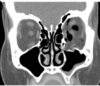

What is the name for this basal skull fracture sign? [1]

A

Hemotympanum